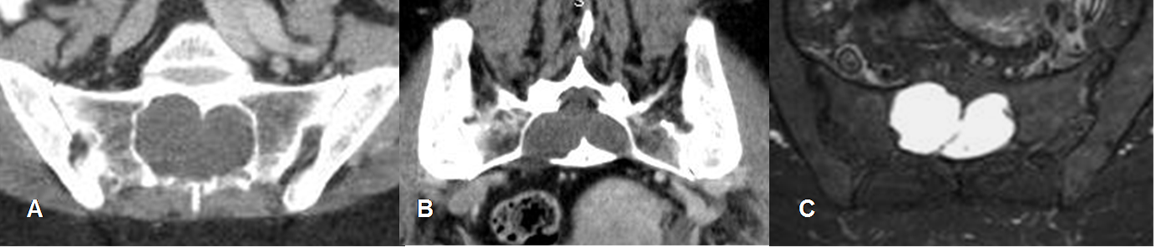

Fig 228. Quiste radicular.

A: TAC axial, B: TAC coronal y C: RM axial en STIR. Gran lesión de consistencia líquida, que ensancha el canal medular y remodela el sacro, que corresponde a quiste radicular.